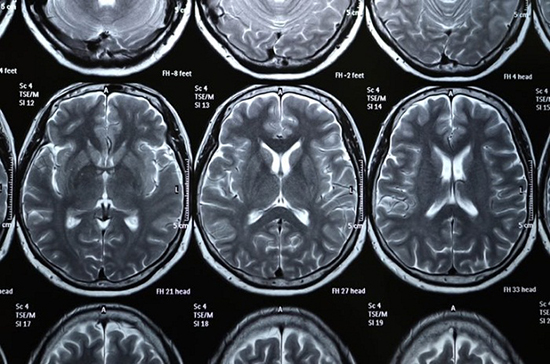

۱- سکته‌ی مغزی

سکته‌ی مغزی یکی از شایع‌ترین عوامل مرگ و میر در دنیا است. این حالت زمانی رخ می‌دهد که یک لخته، یکی از رگ‌های خونی مغز را مسدود می‌کند (یا رگ خونی‌ای پاره می‌شود) و به همین دلیل دیگر به مغز به اکسیژن نمی‌رسد. در صورت وقوع سکته‌های ایسکمیک مغزی، استفاده از دارو‌های حلال لخته‌ی خون می‌تواند نجات بخش باشد، اما این دارو‌ها معمولاً فقط ظرف سه ساعت بعد از وقوع سکته کارساز هستند.